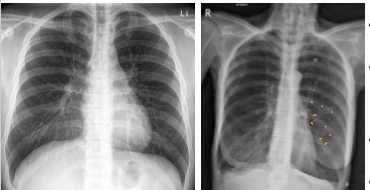

What is going on in these pictures. Whats the dx?

Left pic: normal

Right pic: COPD